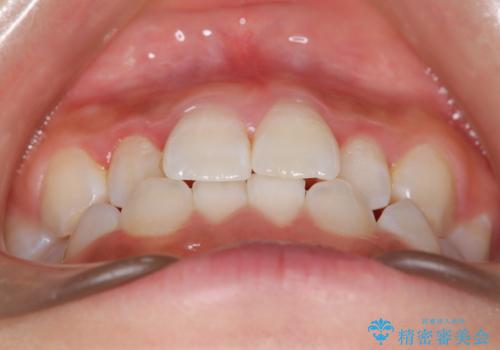

- 子供のころに矯正治療をされていたが、後戻りをしてしまったという20代女性の患者様です。上顎左右の2番が、咬合時に下顎の歯よりも内側に入っているクロスバイトという状態でした。奥歯の咬合関係は変えずに、マウスピース矯正にて前歯の並びを綺麗なアーチに仕上げました。再度後戻りしてしまうリスクを軽減させるために、リテーナー(保定装置)をお渡ししています。